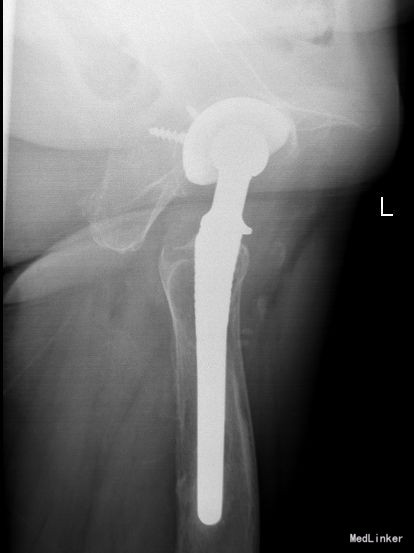

望:神志清,精神尚可,面色微黄,营养良好,体型中等,舌红,苔薄黄;闻:语声重浊,呼吸均匀,未闻及特殊气味;切:脉弦紧。蹒跚步态,跛行步入病房。左髋部前外侧见一弧形切口瘢痕长约18cm,双下肢不等长,左侧较对侧缩短约1cm,左大腿肌肉萎缩,左腹股沟饱满,局部压痛,左髋关节活动度:屈曲90°-30°后伸,外展内收45°,外旋40°,内旋50°,四字征阳性,纵向叩击痛阳性,左髋部外展肌力Ⅲ级,右髋部外展肌力Ⅳ级,左髋部屈髋肌力Ⅲ级,右髋部屈髋肌力Ⅳ级。腰椎后凸侧弯畸形,腰椎活动受限,卧床翻身困难,腰椎棘突及棘突间隙未查及压痛及放射痛;双下肢皮肤感觉无异常,双下肢末梢血液循环可。X线检查:左髋臼股骨头、颈为假体替代,位置可,假体柄与周围骨质吻合,假体髋臼上缘见螺钉状金属内固定影。

术后复查X线片示假体位置良好,固定牢靠。根据中医辨证论治:患者肝肾亏虚,筋骨不通,骨失充则骨蚀增生,筋失养则筋萎挛缩,关节屈伸不利,疼痛,舌质淡,苔白,脉弱,主虚,证属“肝肾亏虚”,术后兼有气滞血瘀,治疗滋补肝肾、佐以活血化瘀药物口服。术后嘱患者中医调护:避风寒,调饮食,慎起居,畅情志;保持切 口清洁,预防感染,注意饮食营养,多吃蔬菜、水果及含蛋白质高的食品,不能进食辛辣刺激类食物。继续口服药物治疗。继续抗炎、抗凝、抗骨质疏松治疗,预防关节术后并发 症;如遇身体局部及全身感染,及时就诊,继续口服利伐沙班或阿司匹林预防血栓性疾病。药物对症处理,适当功能锻炼,主动被动进行关节的 伸直,弯曲,直腿抬高训练,促进关节功能恢复;积极治疗内科基础病,控制血压,预防内科并发症,复查切口愈合情况。避免跪姿,跑跳,深蹲等剧烈活动,按时复诊;助行器使用到复查。不适随诊。本病例中医药应用结合手术治疗,可迅速缓解患者症状,恢复患肢功能,加快术后恢复,可使患者获得满意的术后疗效。